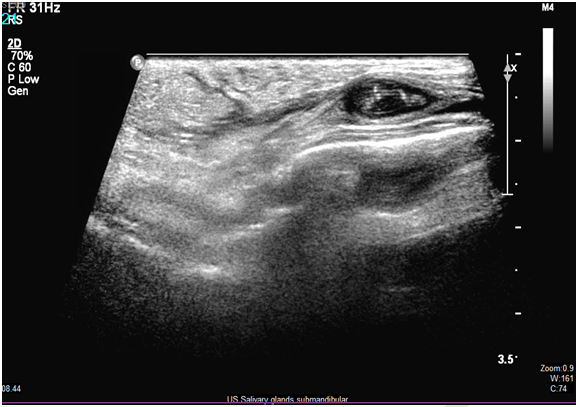

Ultrasound of the swelling was done for further workup, which showed "a well-defined cystic area with tubular echogenic structure within masseteric muscle suggestive of the remote possibility of the parasitic infestation, Parotid and submandibular glands were normal (Figure 1) (Figure 2) (Figure 3).

Figure 1: A well-defined cystic area with tubular echogenic structure within masseteric muscle.

Figure 2: Clear tubular echogenic structure (worm) within masseteric muscle.

Figure 3: Tubular echogenic structure inside well defined cyst within masseteric muscle.

In our case, the diagnosis was suspected by USG (Figure 1) (Figure 2) (Figure 3), which showed a well-defined cystic area with tubular echogenic structure within masseteric muscle. The diagnosis was confirmed by serology test, ELISA positive IgG antibodies for Paragonimus westermani. However, most imaging diagnosis will be radiograph, CT scan of chest or brain or MRI scan. A diagnosis made by US, like in our case has not been reported.